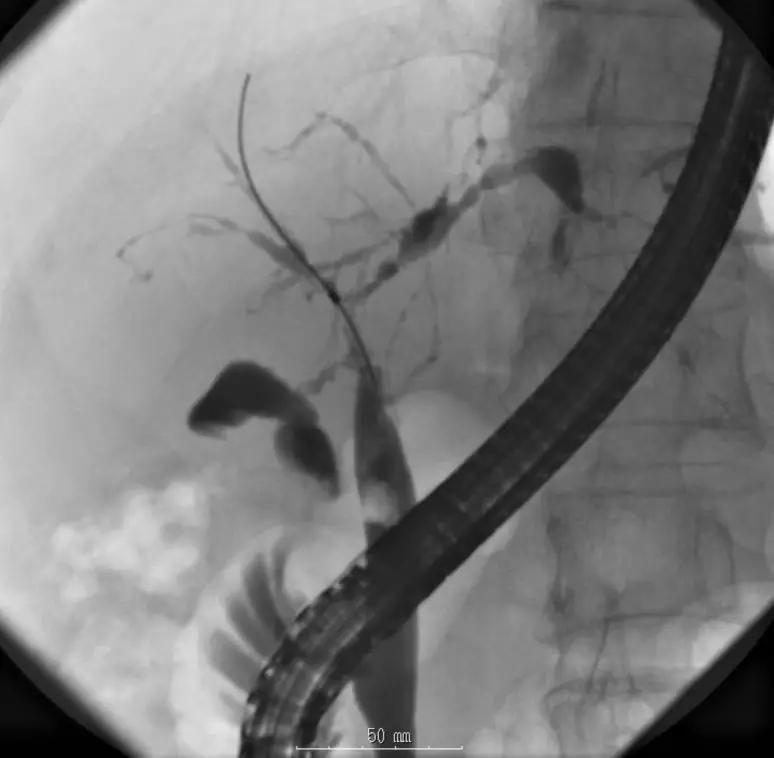

A.胆道影像学检查

ERCP:胆管狭窄与扩张交互,呈串珠状改变

多发短小狭窄,胆管环状受累

PTCD:胆管呈边缘不整羽毛状

ERC:胆管壁呈憩室样突出